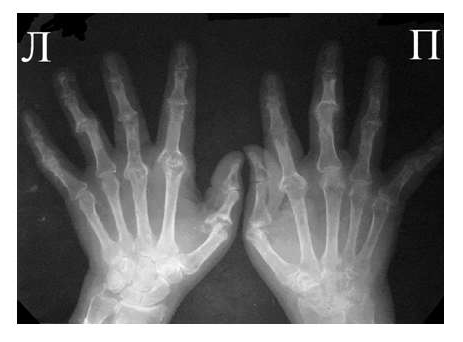

Рис. 3. Обзорная Rо-графия кистей.

Множественные артрозы дистальных и проксимальных межфаланговых суставов. Множественные узелки Гебердена и Бушара. Выраженный артроз 1-го левого запястнопястного сустава